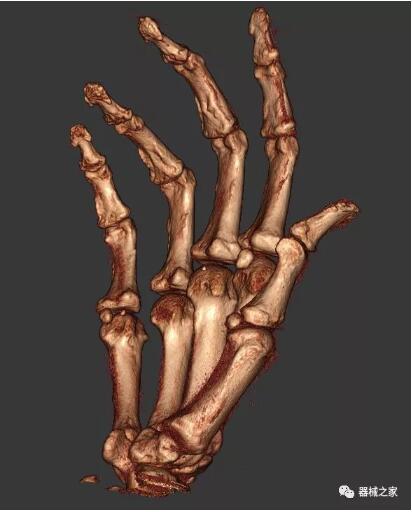

另外一款被稱為世界上最小的CT,它的重量僅300磅,不僅能夠掃查足部,還可以檢查膝蓋和上肢等。

與上面介紹的CT一樣,它同樣具有輻射低、占地空間?。?3*36)的特點,隨開隨用(支持直接接入墻上的插座)。

這款CT使用非常方便,通過上下移動保持與患者的手臂或者雙腿齊平,掃描快速,僅需要30秒左右就可以完成掃查。

以下是這些“特立獨行”的CT所拍出來的圖像: